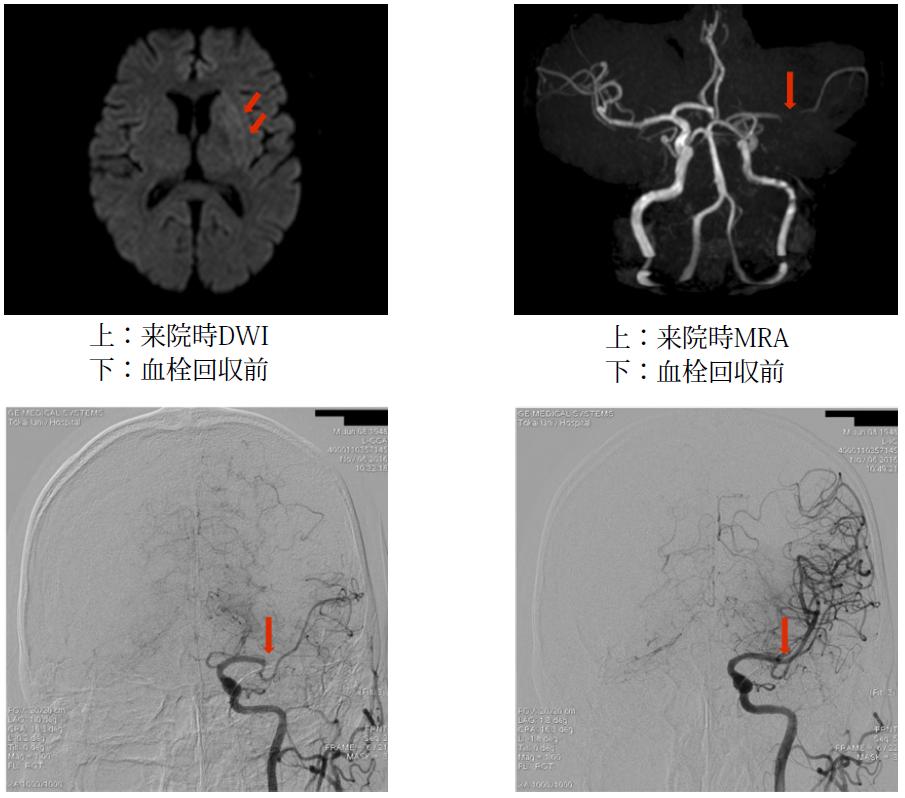

写真:急性期脳梗塞患者さんの具体的事例を示す。右半身の完全片麻痺で発症し、発症から33分で当院に搬送された。来院時頭部MRI 拡散強調画像(DWI)では左基底核に高信号を認め、magnetic resonance angiography(MRA)では、一側の中大脳動脈が閉塞していた。来院後45分で血栓溶解療法を行い、78分で血管内治療を行い、発症から138分で完全再開通が得られた。入院後心房細動が検出され、心房細動による心原性脳塞栓症と診断し、新規抗凝固薬を導入し、2週間後独歩にて自宅退院した。以上のごとく、本例では血栓溶解療法、血管内治療による急性期治療の有効性が示された。